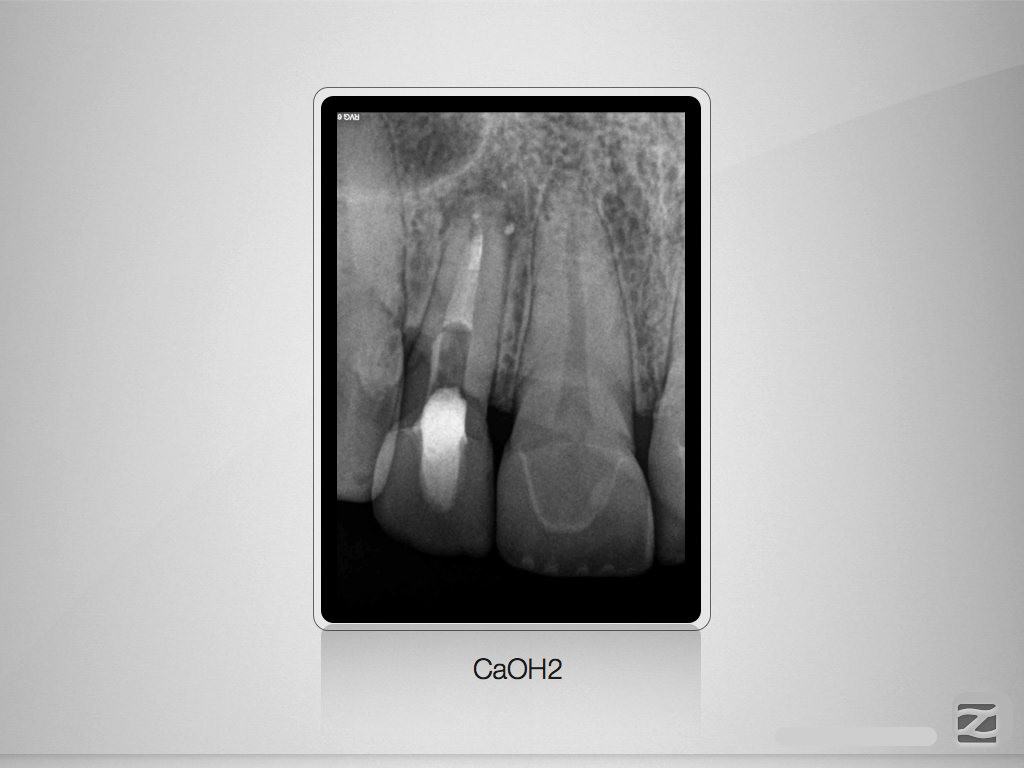

Der Schein trügt